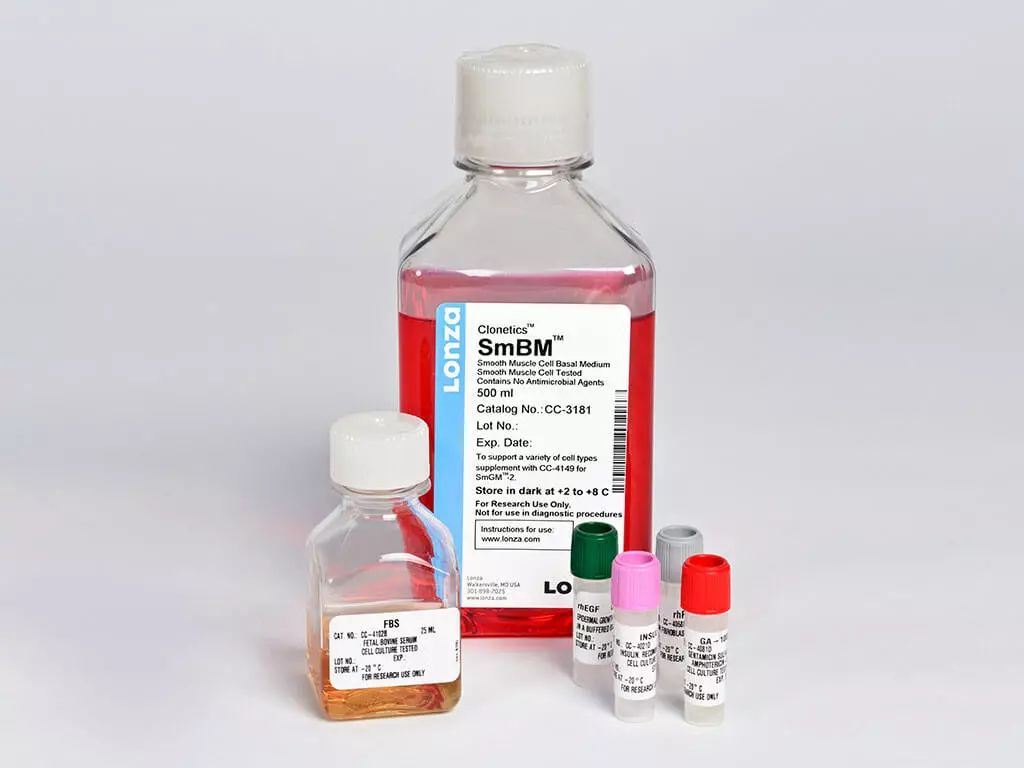

四、LONZA原代血管平滑肌细胞培养基

货号:CC-3182

中文名称:SmGM-2平滑肌细胞培养基(CC-3181 + CC-4149)

英文名称:SmGM- 2 Smooth Muscle Cell Growth Medium -2 BulletKit

套装组成:SmBM平滑肌细胞基础培养基(货号:CC-3181)、SmGM-2 SingleQuot添加剂及生长因子(货号:CC-4149)

不论正常人还是糖尿病患者来源的血管平滑肌细胞,均可使用SmGM-2进行体外培养。SmGM-2作为一种成熟的原代细胞培养基,常规用于心脏、气道、前列腺、肠道等人体各类平滑肌细胞的培养中,可促使平滑肌细胞快速增殖,其成分包含5%的FBS。